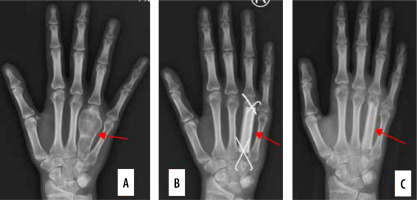

The next set of problems arises with the more popular use of locking plates, especially in the distal radius. We frequently observe malpositioning of the screws, which influences or even destroys normal motion of joints such as the distal radioulnar joint (Figure 2) or causes inflammation leading to chronic rupture of the tendon, which is well depicted in Figure 3 by ultrasonography. These findings can be a reason for the removal of plates or screws, leading to unplanned secondary surgery. In cases of tendon rupture, such as in chronic injury of extensor pollicis longus, tendon transfer is often required for recovery of function [8].

Ulnar screw blocking and chronically damaging the distal radioulnar joint. A) Plain radiogram. B) CT scan showing protruding screw causing ulnar impingement and erosion – red arrow